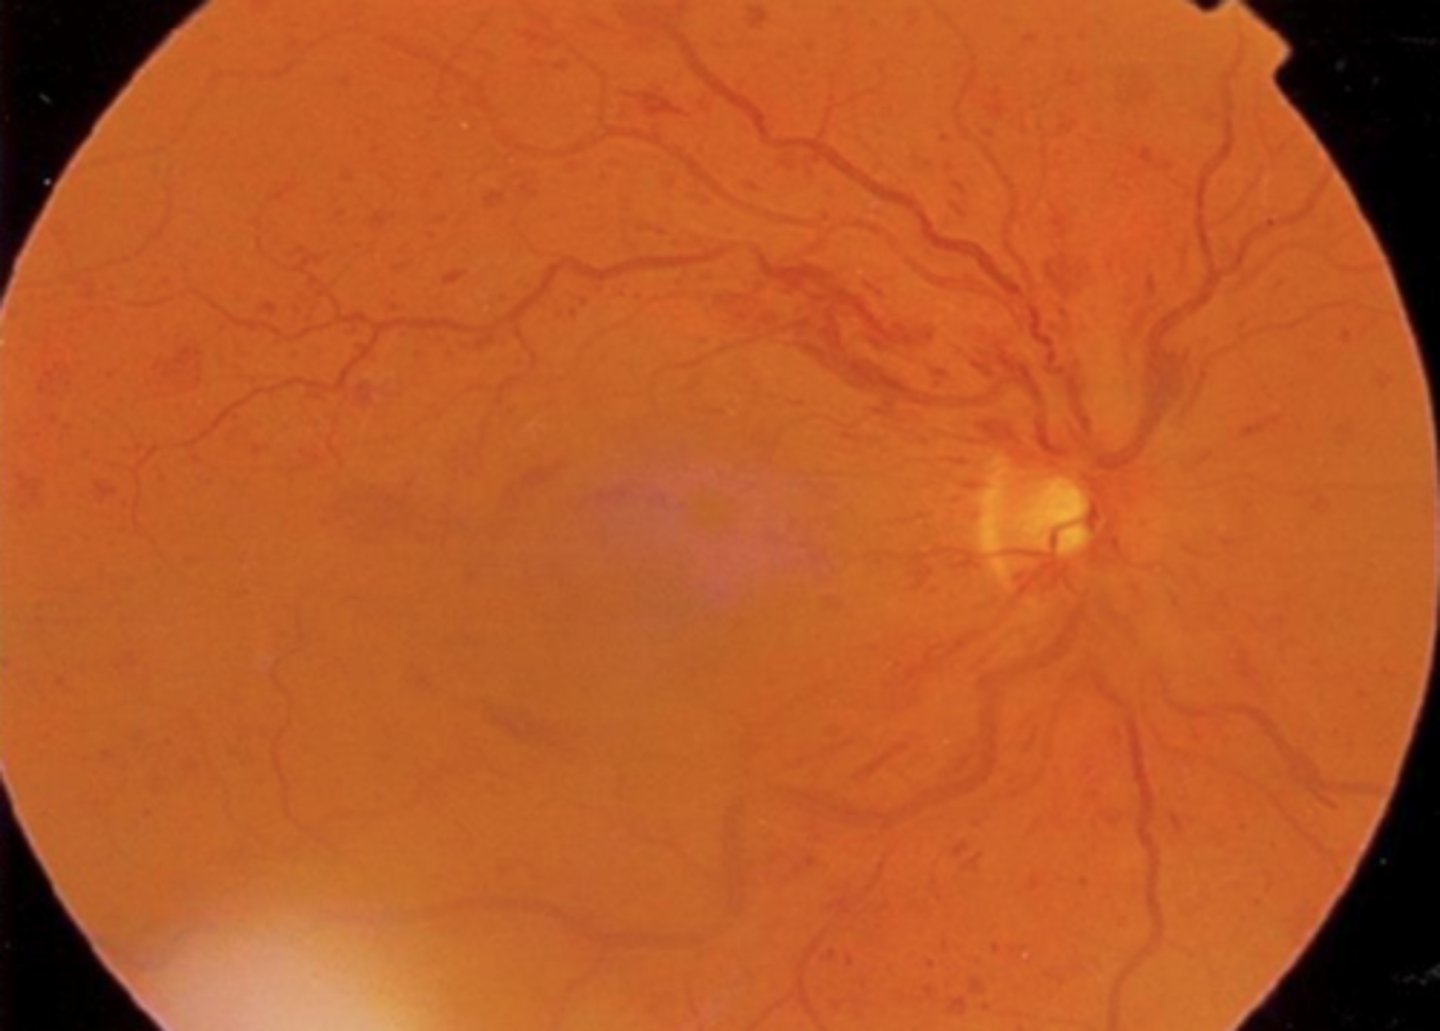

image - ischemic CRVO that shows FANG (low perfusion)

What fundus characteristic makes you sure the CRVO was ischemic?

dark blood red fundus

left - not sure which type

right - must be ischemic

What does CRVO look like on OCTA?

dark areas = non-perfusion (capillary dropout)